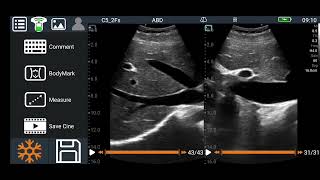

How to measure cervical length on ultrasound??